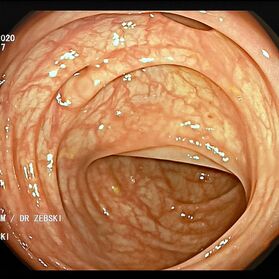

Die Darmspiegelung ist der uneingeschränkte Goldstandard für die Diagnostik und Vorsorge sämtlicher Erkrankungen des Dickdarms und des untersten Dünndarms. Die hochauflösende Bildqualität (High Definition) unserer modernen Videokoloskope ermöglicht eine zuverlässige Einordnung nahezu sämtlicher entzündlicher oder geschwulstiger Veränderungen der Dickdarmschleimhaut.

Die Darmspiegelung hilft, dass Darmkrebs gar nicht erst entstehen kann. Denn während der Untersuchung werden auch Polypen entfernt, aus denen sich der Darmkrebs in der Regel entwickelt. Von allen Maßnahmen zur Früherkennung dieser Polypen besitzt die Koloskopie die höchste Empfindlichkeit. Sie weist kleinste Polypen, aber auch Darmkrebs nach, der noch keinerlei Symptome macht. Die Abtragung dieser Polypen erfolgt direkt, wenn sie entdeckt werden. Das geschieht völlig schmerzfrei. Durch die Abtragung der Polypen kann die Entstehung von Darmkrebs effektiv verhindert und die krebsbedingte Sterblichkeit gesenkt werden.